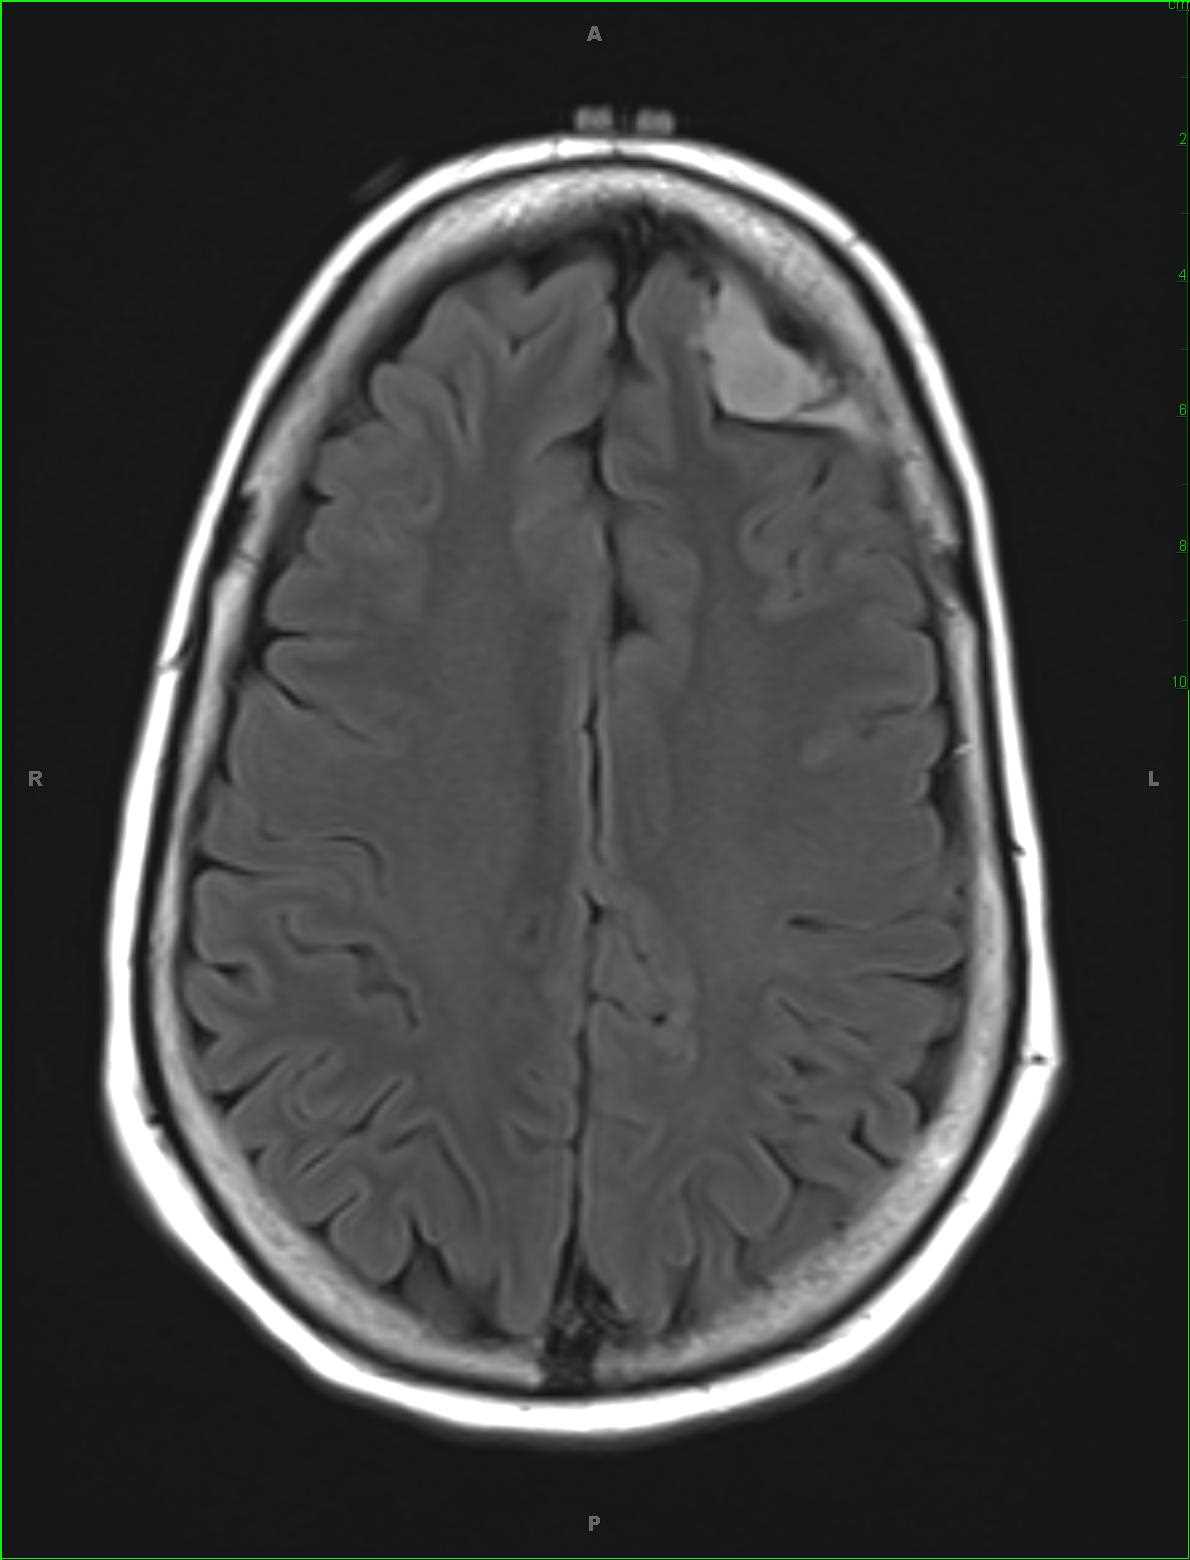

Cortical Dysplasia

Long-standing history of right temporal lobe epilepsy localizing to the superior temporal gyral region on EEG. There is a disorganized appearance of the cortical gray matter along Heschls gyrus on the right. There is thickening of the cortical gray matter which is indistinct on the more lateral sagittal T1-weighted image. A large confluent region of T2/FLAIR hyperintense signal was identified within the superior right temporal gyrus without diffusion restriction or loss of signal on the susceptibility weighted images. No suspicious contrast enhancement is identified. A differential of cortical dysplasia, dysembryoplastic neuroectodermal tumor, ganglioglioma and low-grade astrocytoma was given. On biopsy, the region of signal abnormality was found to reflect a region of focal cortical dysplasia type Ia. Focal cortical dysplasia (FCD) can be divided into two categories, FCD type I (non-Taylor dysplasia) and FCD type II (Taylor dysplasia). FCD type Ia results from dyslamination and mild malformation of cortical development. FCD type Ib results from isolated architectural abnormalities and cytoarchitectural dysplasia. FCD type II can further be subdivided into type IIa, no balloon cells, and type IIb, balloon cells present.